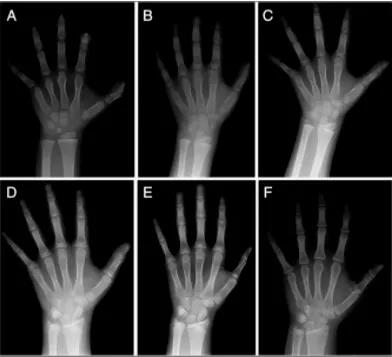

(医生通过左手x光片判读掌指骨和尺桡骨发育程度,确定骨龄大小。)

李医生:很多父母都认为测骨龄是一个很麻烦的事情,其实只需配合完成一次左侧腕关节正位X线光片拍摄即可。如果孩子配合的好,几分钟就能完成。家长也不用担心对孩子身体有伤害,测一次骨龄,孩子接收的辐射量只相当于晒两小时太阳。如果是微剂量测量,那么辐射量就更小了。